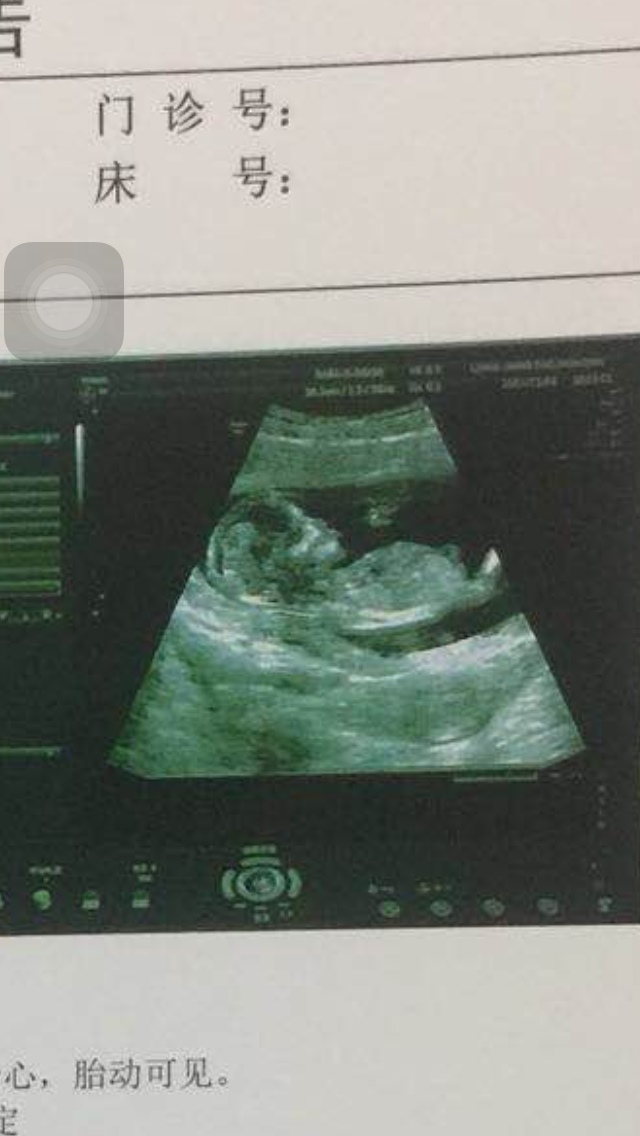

孕19周+5天

看起来是个男孩子